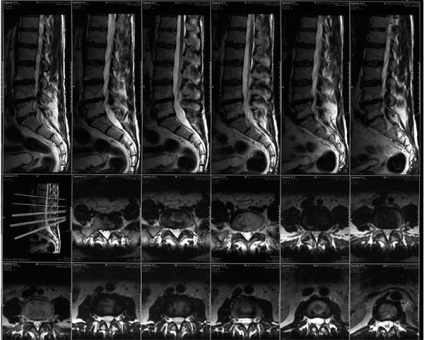

MR kép az eredeti

Mágneses rezonancia képalkotás minden gerinc kezdődik egy gyors vizsgálat a sagittalis síkban gradiens echo. Ez a szakasz a vizsgálat mindössze 10-30 másodperc. Ezután, hogy a készítmény a T-1 és T 2 súlyozott tomogramok sagittalis és axiális síkban.

A tanulmány a gerinc szerkezete optimálisan elvégezni T1-WI. A képadatok által meghatározott gerincvelő, mint egy homogén struktúra egy hiperintenzív jelet. Subarachnoidális térben és szalagok alacsony jel intenzitását. A jel a csigolya egy inhomogén szerkezetű: kompakt csontanyagot a csigolyatestek és folyamatok, körgyűrű és végtárcsák hypointense jelet csontvelő csigolyatestek olyan jelet állít elő a mérsékelt intenzitású. Csakúgy megkülönbözteti egy lófarok vizsgál.

Jellemző értékei MRI ágyéki gerinc: a méret a dura sac 12-15 mm (elöl-hátul dimenzió), gerinccsatorna szélessége 21-29 mm (csatorna bővítése fokozatosan történik az egész).